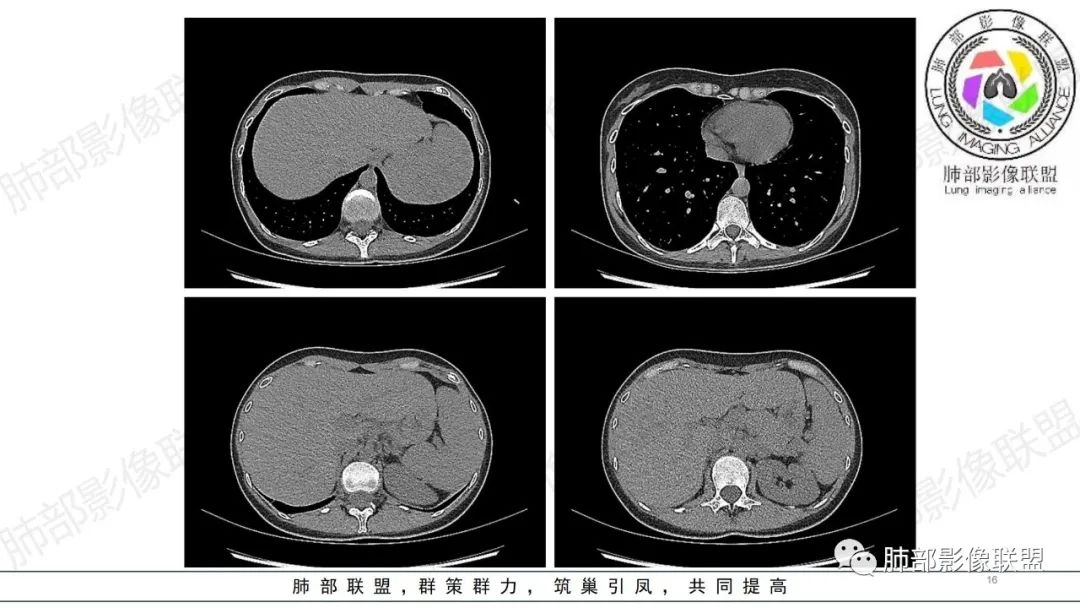

34岁女性患者,“哮喘”病史30年,近期有可疑刺激性气体吸入史;因乏力半年,咳嗽、憋气、发热4天就诊;6.1CT提示双肺广泛毛玻璃影及粟粒样结节,胸膜下闲置及血管周闲置,可见树丫征,部分小叶间隔增厚。考虑:1.过敏性肺泡炎,有可疑刺激气体接触史,胸膜下闲置,广泛毛玻璃影,地图样分布,粟粒结节边界模糊,支持过敏性肺泡炎,但糖皮激素治疗效果不佳,且动态复查血常规血红蛋白进行性降低,过敏性肺泡炎 不符合;2.肺含铁血黄素沉积症:患者30“哮喘”病史,可能为肺含铁症状,肺部CT提示双肺弥漫毛玻璃影及粟粒结节影,中下肺明显,肺底部分小叶间隔增厚,近期咳嗽、憋气、发热,血常规血红蛋白进行性下降,考虑肺含铁急性期症状,但临床无咯血症状,肺含铁不典型。综合考虑:肺含铁血黄素沉积症>过敏性肺泡炎。

肺内气腔磨玻璃结节,肝脾肿大,治疗后间质改变,弥漫大B可能

年轻女性 ,急性喘息发热,肺部影像弥漫磨玻璃密度,部分细小腺泡结节,胸膜下黑线显示,短期复查,病变密度增高,下肺明显,血管周围肺组织累及较少、且逐渐成小叶间隔分布。考虑弥漫肺泡内病变,并经淋巴道转移,下肺比上肺明显,多为免疫细胞功能下肺较强。1.过敏性肺泡炎,有相关病史,三层密度特点、头尾测分布,符合。2 肺泡微石症,多有钙化,且缓慢起病,病程不太符合,放待排。3 吸入相关肺损伤,有病史,疾病演变过程也符合渗出-肉芽肿改变,建议详细询问病史。4 感染性病变,结核?病变气道分布为主,如此弥漫且没有树丫不符合。5.巨细胞病毒,可以磨玻璃 结节 改变,没有免疫缺陷病史。最后考虑吸入所致 1过敏性肺泡炎、吸入性肺损伤 鉴别肺泡微石症。